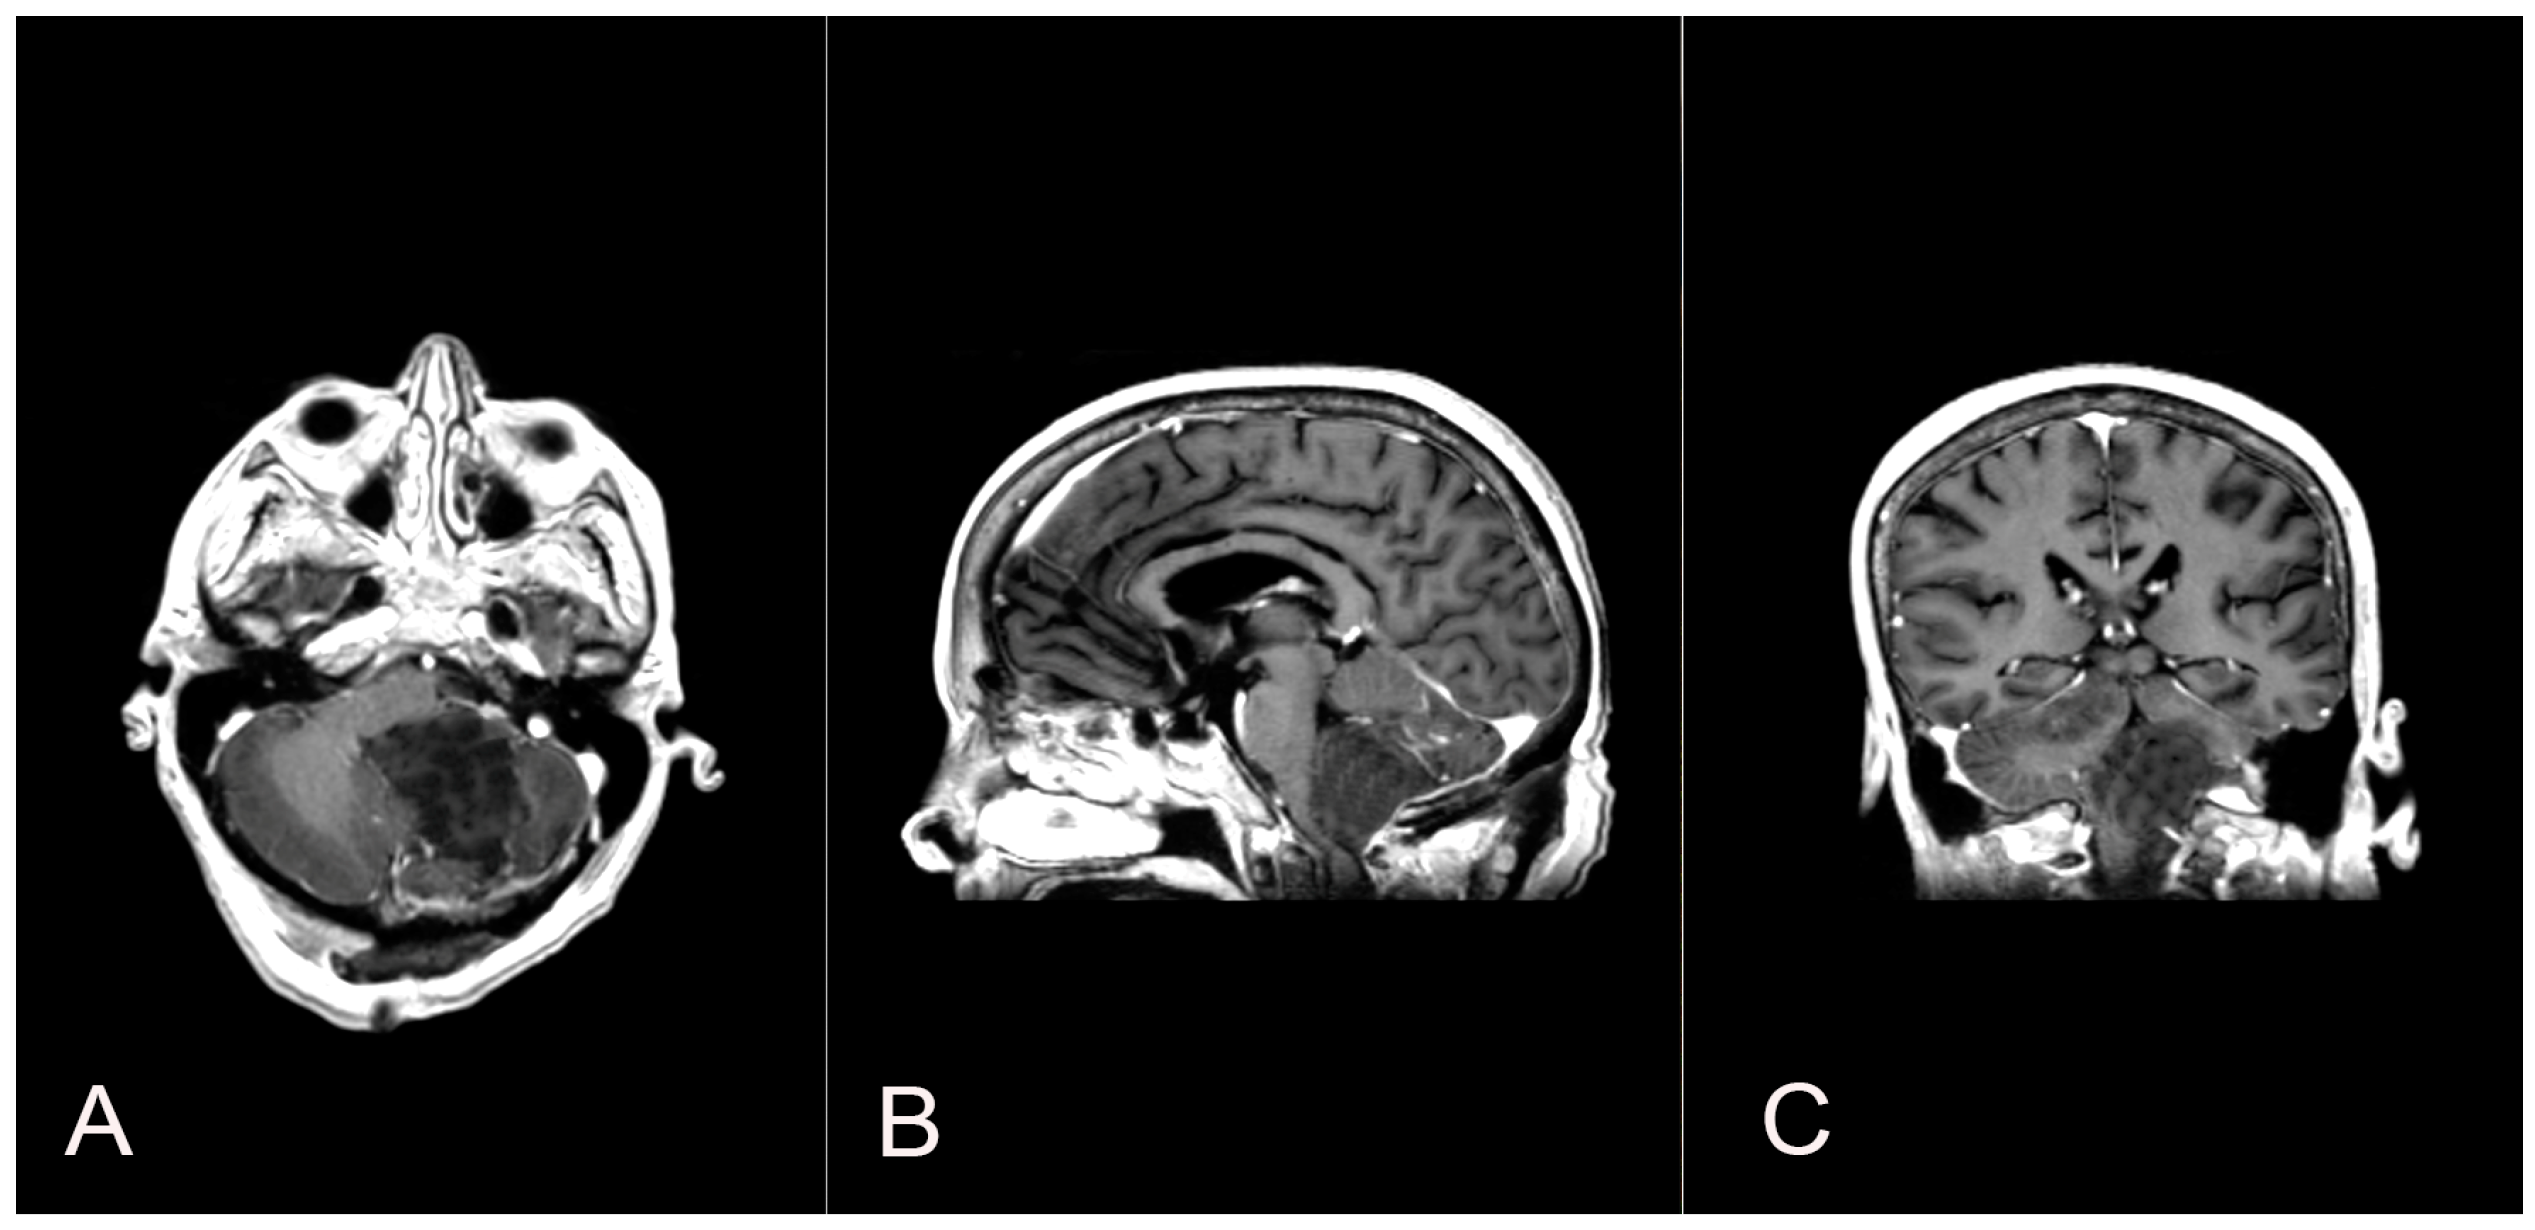

A 58-year-old woman presented with nausea, headache and gait instability. A brain contrast-enhanced magnetic resonance imaging (MRI) device documented an expansible lesion in the left cerebellar hemisphere involving the middle-lower cerebellar pedicle surrounded by perilesional edema (measures: transverse diameter: 3.2 cm; sagittal diameter: 3 cm). Compression of the IV ventricle and cerebellar tonsils herniation in the foramen magnum were present. Also, tri-ventricular obstructive hydrocephalus was present (Figure 2). The patient underwent ventricular shunt and microsurgical exeresis of the lesion via left suboccipital craniectomy (Figure 3). The histopathological examination documented a grade I glioneuronal lesion. After the first operation, the patient underwent adjuvant radiotherapy treatment with a total of 54 Gy in 27 sessions, with daily fractionation of 2 Gy/day. Clinical and radiological follow-up was then recommended.

Figure 3.

Axial (A), sagittal (B) and coronal (C) postoperative T1 contrast-enhanced brain MRI shows the left suboccipital craniectomy accomplished and the GTR exeresis of the lesion.